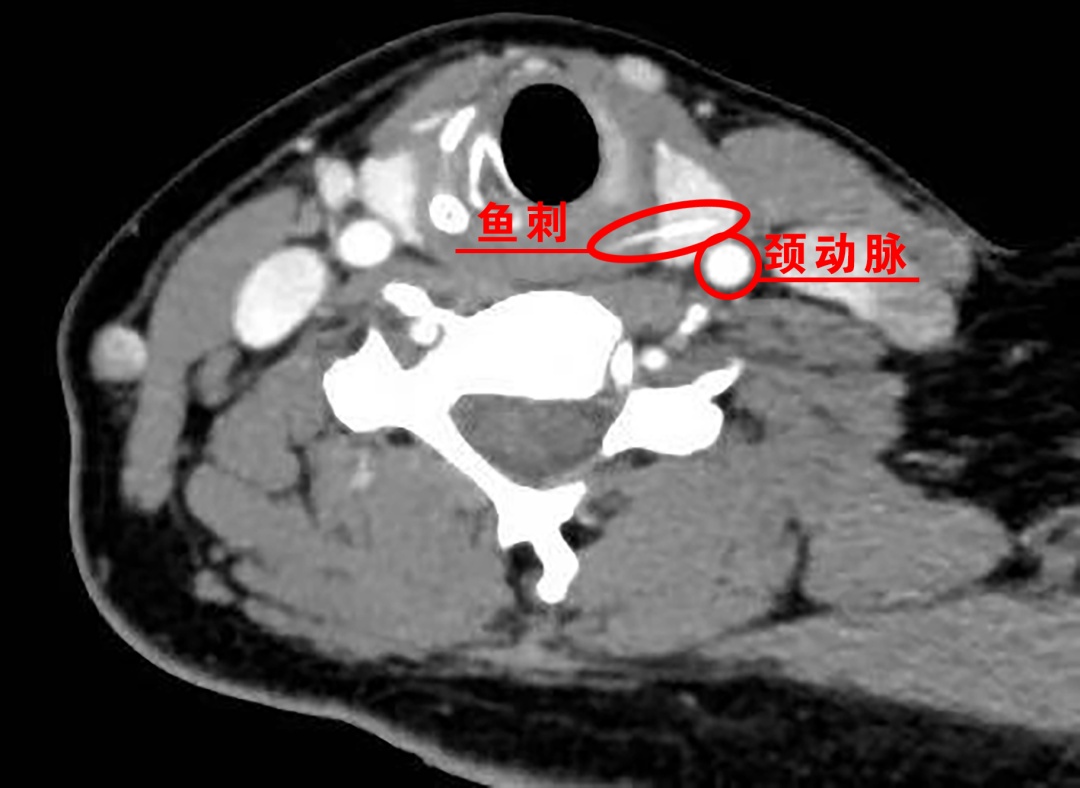

张女士入院后,颈部增强CT检查结果很快揭示了问题的关键:食管入口偏左侧可见一条约1.7厘米的高密度条状影,已穿破食管扎进了甲状腺组织,鱼刺末端距离左侧甲状腺被膜(紧邻左侧颈总动脉)仅约3.4毫米。

鱼刺扎进甲状腺绝非小事,不仅会带入细菌引发严重的深部脓肿甚至致命的纵隔感染,更因紧邻颈动脉等大血管,随时可能因移位刺破血管导致瞬间大出血休克;同时,它还极易损伤喉返神经造成声音嘶哑或呼吸困难,若长期滞留更会形成难以愈合的瘘管。